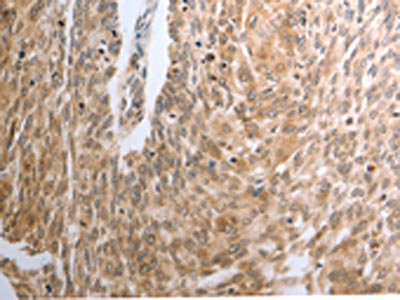

The image on the left is immunohistochemistry of paraffin-embedded Human cervical cancer tissue using CSB-PA283902(RAD51 Antibody) at dilution 1/30, on the right is treated with synthetic peptide. (Original magnification: ×200)

The image on the left is immunohistochemistry of paraffin-embedded Human esophagus cancer tissue using CSB-PA283902(RAD51 Antibody) at dilution 1/30, on the right is treated with synthetic peptide. (Original magnification: ×200)